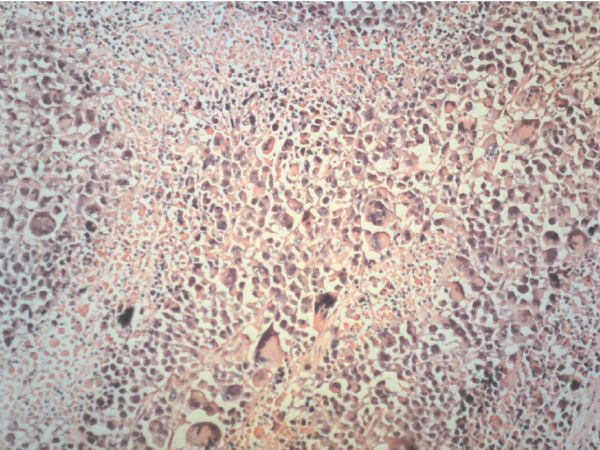

Lihui WANG, Lianhong LI, Shen LV, Shujun FAN, Li ZHAN, Bo WANG, Zhong ZHANG

The invasion and metastasis of breast cancer are supposed to involve several stages in which epithelial-mesenchymal transition (EMT) is regarded as the mechanistic basis for the behavior of cancer cells. A series of factors related to EMT are apparently involved in such process. The current study aimed to investigate the contributions of EMT and related factors in lymph node metastasis of breast cancer. The expressions of E-cadherin (E-Cad), N-cadherin (N-Cad), vascular endothelial cell growth factor (VEGF), matrix metalloproteinase-9 (MMP-9), cyclooxygenase-2 (COX-2), and CD34 were examined in 74 cases of breast cancer, including 39 cases with lymph node metastasis and 35 cases without lymph node metastasis by immunohistochemistry. Multivariable Cox proportional hazards model was used to analyze the patients’ prognosis. The expressions of N-Cad, VEGF, MMP-9, and COX-2 in cases with lymph node metastasis were significantly higher than those without lymph node metastasis (P<0.05), while the E-Cad level was inversely related to status of lymph node metastasis (P<0.05). The metastasis rate of lymph node in the cases with EMT (lower E-Cad expression and higher N-Cad expression) was 78.3%, while that without EMT (higher E-Cad expression and lower N-Cad expression) was 11.1%. There was a statistical difference in the expression of COX-2 protein between histological grade I and grade II or III, respectively (P<0.05). In the cases with higher grade, the expression of E-Cad was decreased, while that of N-Cad was increased. Higher microvascular density (MVD) was also found to be significantly associated with lymphatic metastasis (P<0.05), and the cases with higher MVD had shorter survival time. This study indicates that EMT and expressions of VEGF, MMP-9 and COX-2, and MVD value are strongly correlated with lymph node metastasis in breast cancer.